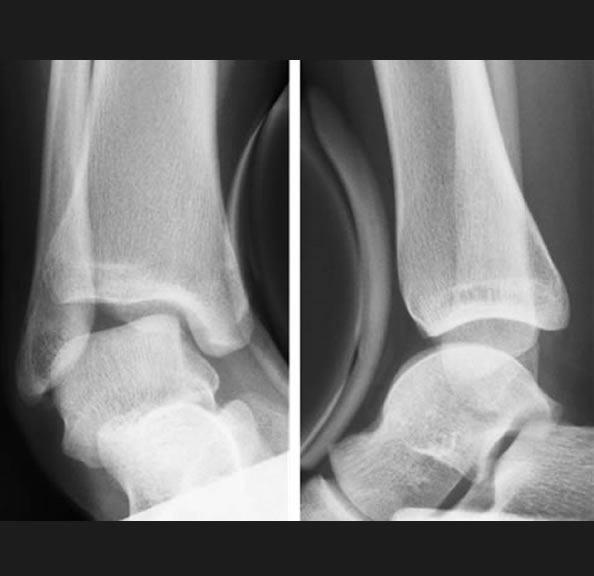

足首の痛みと変形 変形性足関節症、距骨壊死、距骨骨軟骨障害

新鮮骨折と遺残障害 足関節の果部骨折・脱臼骨折、踵骨関節内骨折、距骨骨折

の外科的治療:症例

保存療法では治療が見込めない患者様に対しては、人工足関節置換術、矯正骨切り術、遠位脛骨斜め骨切り術、関節固定術、血管柄付き腓骨移植、再建術などの外科的治療を提案をしております。

外科的治療:症例一覧